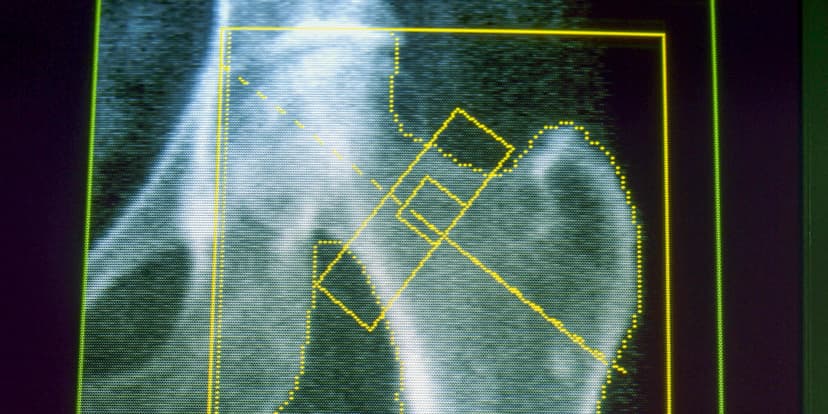

The study observed about a 30% increased risk of osteoporosis and a 12% increased risk of gout for those taking GLP-1 medications compared to individuals not on these drugs. While the observed risks are not substantial, they warrant further investigation. Experts suggest that the rapid weight loss achieved with these medications, or a potential decrease in nutrient intake due to reduced appetite, could be contributing factors to bone health changes.

While this observational study cannot definitively prove causation, the findings align with other research and FDA labeling for semaglutide, which notes a potential increased risk of bone fractures in older adults and women. Some experts point out that lifestyle factors, such as structured exercise when combined with GLP-1s, may mitigate bone density loss, highlighting the importance of comprehensive obesity treatment strategies.